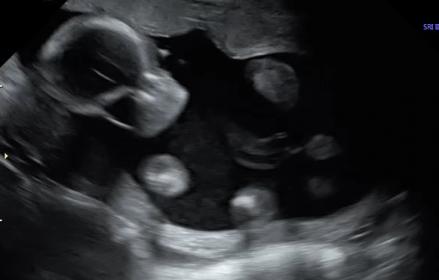

Team Green No Longer ??? 20 week scan

Hi! I recently went to my 20 week scan with the intention of being team green! All went well during the scan and I didn't see any definitive "bits". The pictures the tech sent me didn't seem to give any clues....but then I make the mistake of watching the DVD with live shots. I seems like there is a brief glimpse of boy parts in the shot where the baby is facing forward. It looks like a potty shot, but I haven't seen any with the skull visible, so I am not sure what to think. I'm hoping that I am still team green, but these shots make me think otherwise. Any insight would be greatly appreciated!! I am going crazy trying to figure it out. :shrug:

Attachment 42608Attachment 42609Attachment 42610